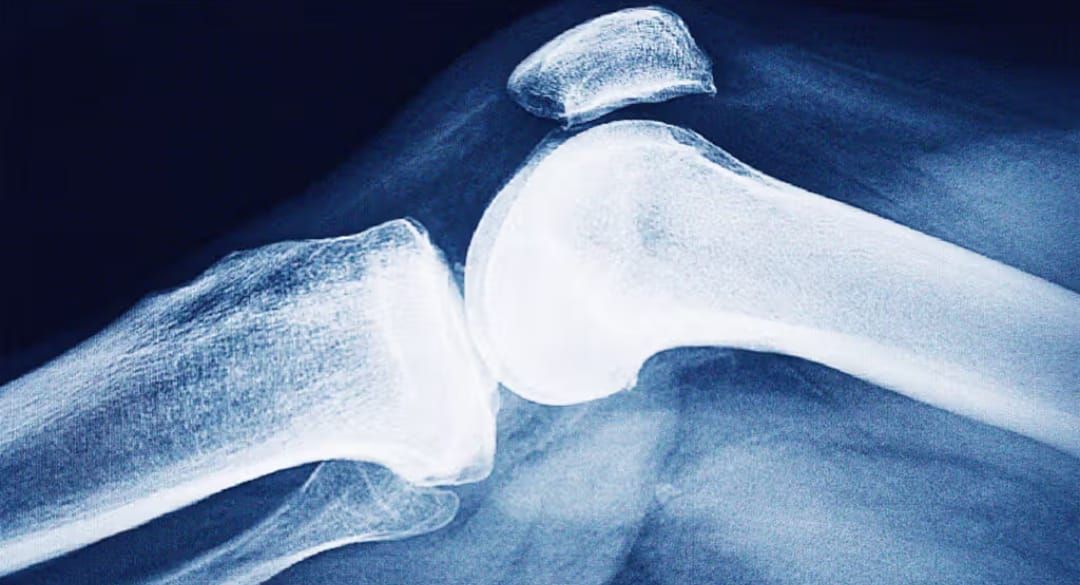

Osteoporosis weakens bone and exposes people to so-called “fragility” fractures (a fall from standing height, a trivial movement). Long asymptomatic, it often declares itself with a first fracture – vertebra, wrist, hip – which is likely to be followed by others if nothing is done. Each October, the International Osteoporosis Foundation (IOF) underscores the scale of the burden and the need for a systematic post-fracture care pathway.

A reduction in bone mass and quality, and therefore in its strength, with an increased fracture risk. Diagnosis relies on bone densitometry (DXA): a T-score ≤ −2.5 at the spine or hip confirms osteoporosis, even without a fracture. “Peak bone mass” is built up into adulthood, remains stable until around age 40, then declines by about 1–2% per year; after menopause, loss accelerates due to estrogen deficiency.